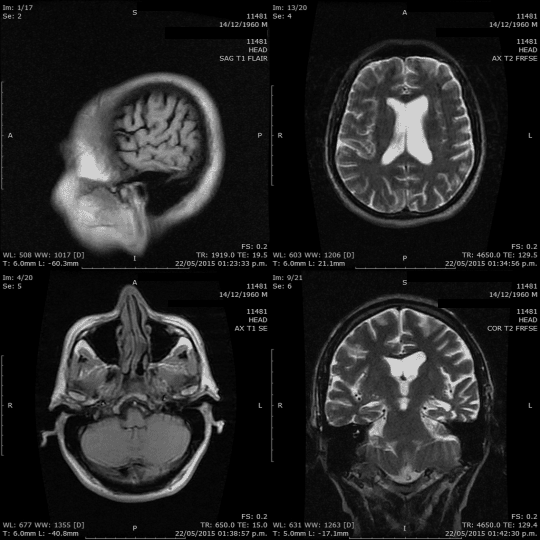

When it comes to understanding the brain, we have a variety of tools at our disposal: CT scans, MRIs, PET scans, mammograms, ultrasounds, X-rays, and more. These tools aren’t just fancy names; they play a crucial role in helping us see inside the brain, highlighting potential issues and conditions. Our goal? Spotting problems early, ensuring accurate diagnoses, and providing effective treatments.

Anomaly detection in medical data serves as a vigilant guard, ensuring that no irregularity remains unnoticed. Imagine this: Among numerous routine MRI scans depicting typical brain structures, one scan presents a distinctive pattern—perhaps an unusual concentration of neural activity or an atypical tissue formation. Such anomalies could hint at early-stage conditions or previously unrecognized physiological phenomena.

Diagnostic Imaging: Detecting irregularities in MRI, CT, or X-ray images that may indicate potential health issues.

Brainomaly explores the intricacies of the Alzheimer’s disease dataset. This dataset comprises a mix of T1-weighted brain MRIs from healthy controls and patients with Alzheimer’s disease. It provides a rich landscape for Brainomaly to showcase its ability to discern subtle structural changes indicative of neurologic diseases.